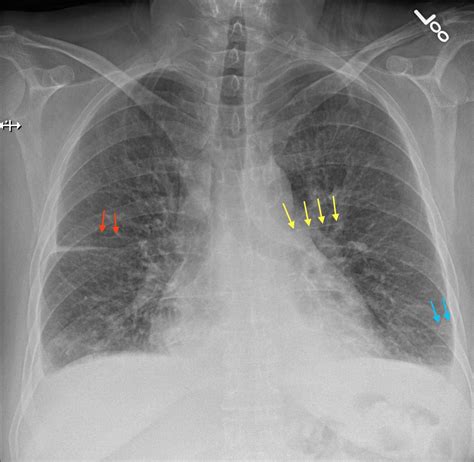

Interpreting Kerley B Lines on CXR

Interpreting Kerley B lines on a CXR requires a systematic approach. Here are the steps involved:

• Identify the Location: Kerley B lines are usually found in the peripheral lung fields, particularly in the costophrenic angles.

• Assess the Pattern: Look for short, horizontal, linear opacities. These lines are typically less than 1 cm in length and are often seen in clusters.

• Evaluate the Context: Consider the clinical context and other findings on the CXR. Kerley B lines are often accompanied by other signs of pulmonary edema, such as alveolar opacities and pleural effusions.

• Differentiate from Other Findings: Kerley B lines can sometimes be confused with other linear opacities, such as those seen in interstitial lung diseases. Careful evaluation of the pattern and distribution can help differentiate Kerley B lines from other findings.